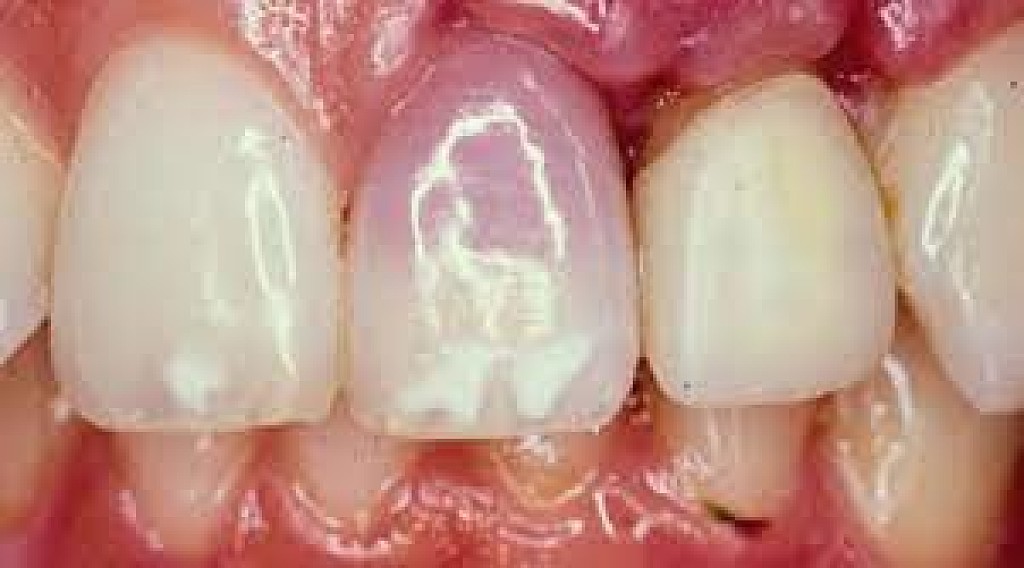

A bruised tooth is often caused by an injury to the tooth. Similar to a bruise on your skin, a bruised tooth is a reaction to excess pressure or force. While your tooth won’t turn black and blue like your skin, it can become discolored and turn a gray tint.

Identifying a Bruised Tooth

A bruised tooth is painful and may ache because the soft tissue and ligaments around your tooth essentially absorb the impact of the trauma or injury. Just like a bruise on your skin, the capillaries around the injured tooth burst. The capillaries then travel to the opening of the tip of the root, which gives the tooth a pinkish discoloration.

The pinkish discoloration may turn gray, which can be permanent. A gray tooth may mean that the pulp inside your tooth is impacted, resulting in a higher risk of infection or decay. This can result in the need for a root canal Brentwood. If your tooth does not turn from pink to gray, you may be in the clear. However, you should see the best dentist Brentwood has, as they will want to monitor your tooth and help you in identifying a bruised tooth.